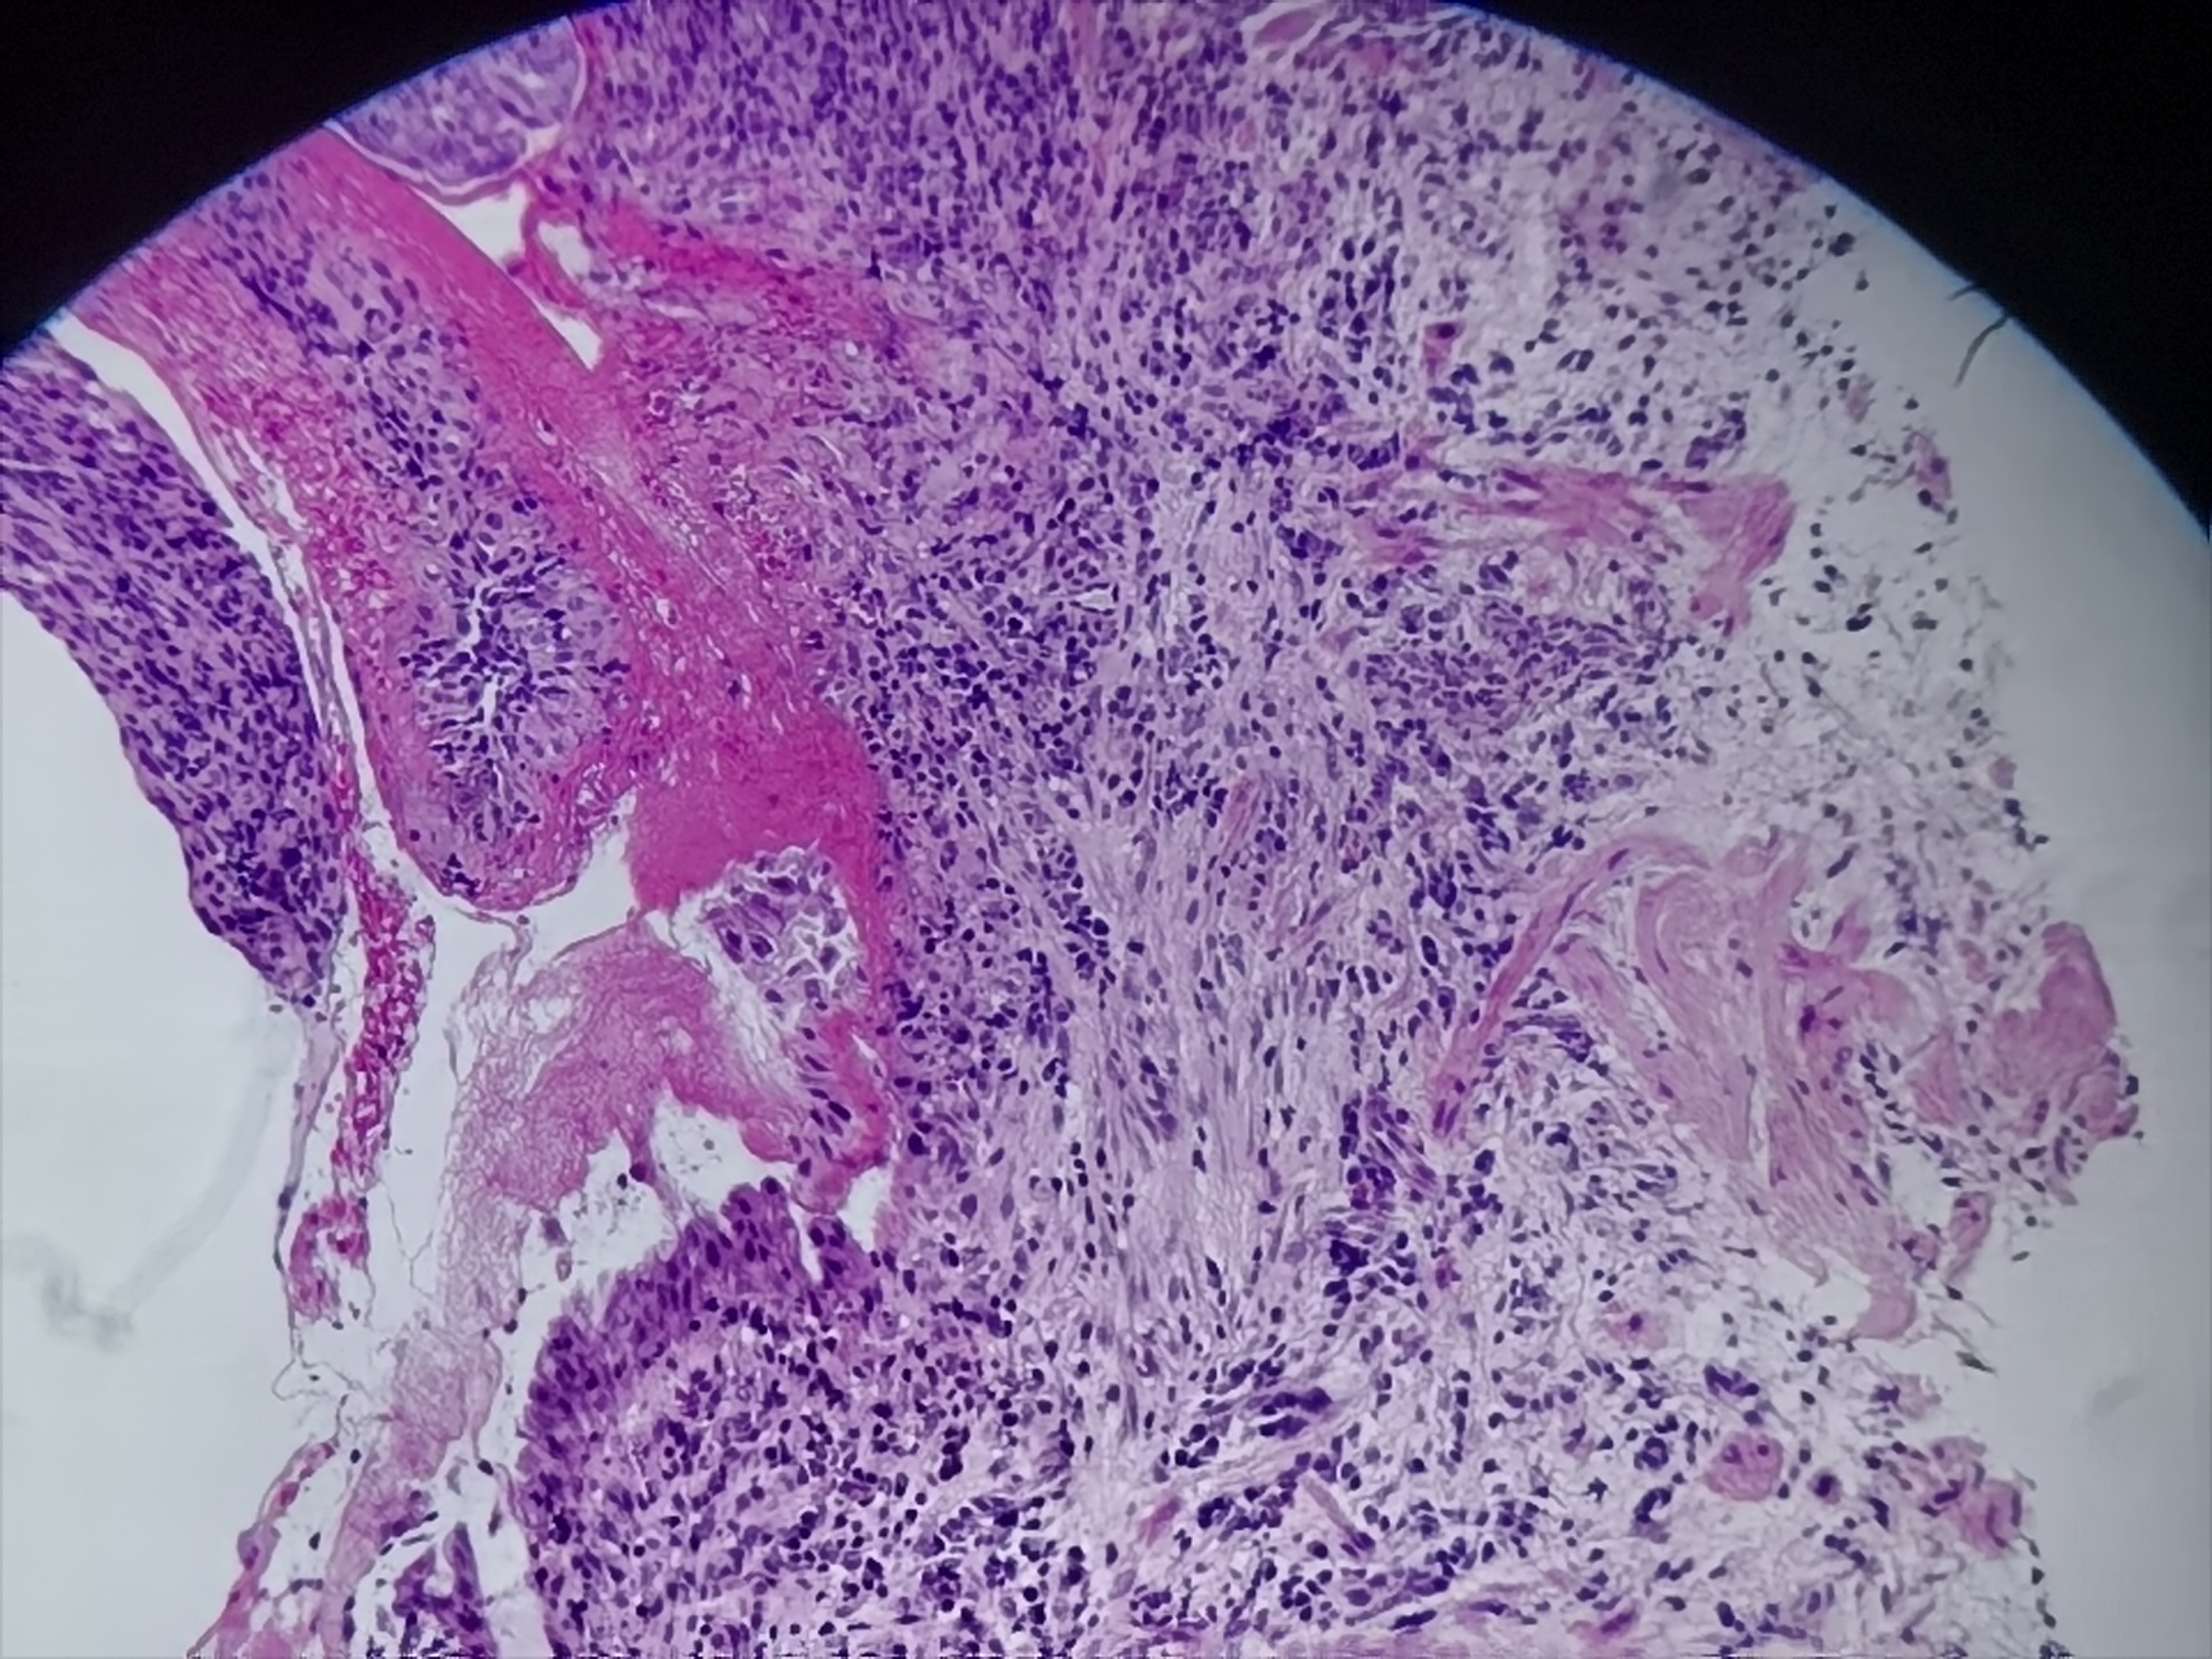

食管活检

性别

男

年龄

58岁

临床诊断

食管术后、反流性食管炎、残胃

一般病史

食管:可见多枚糜烂

标本名称

食管粘膜活检

大体所见

灰白色组织1块

图1

重度慢性活动性炎+糜烂